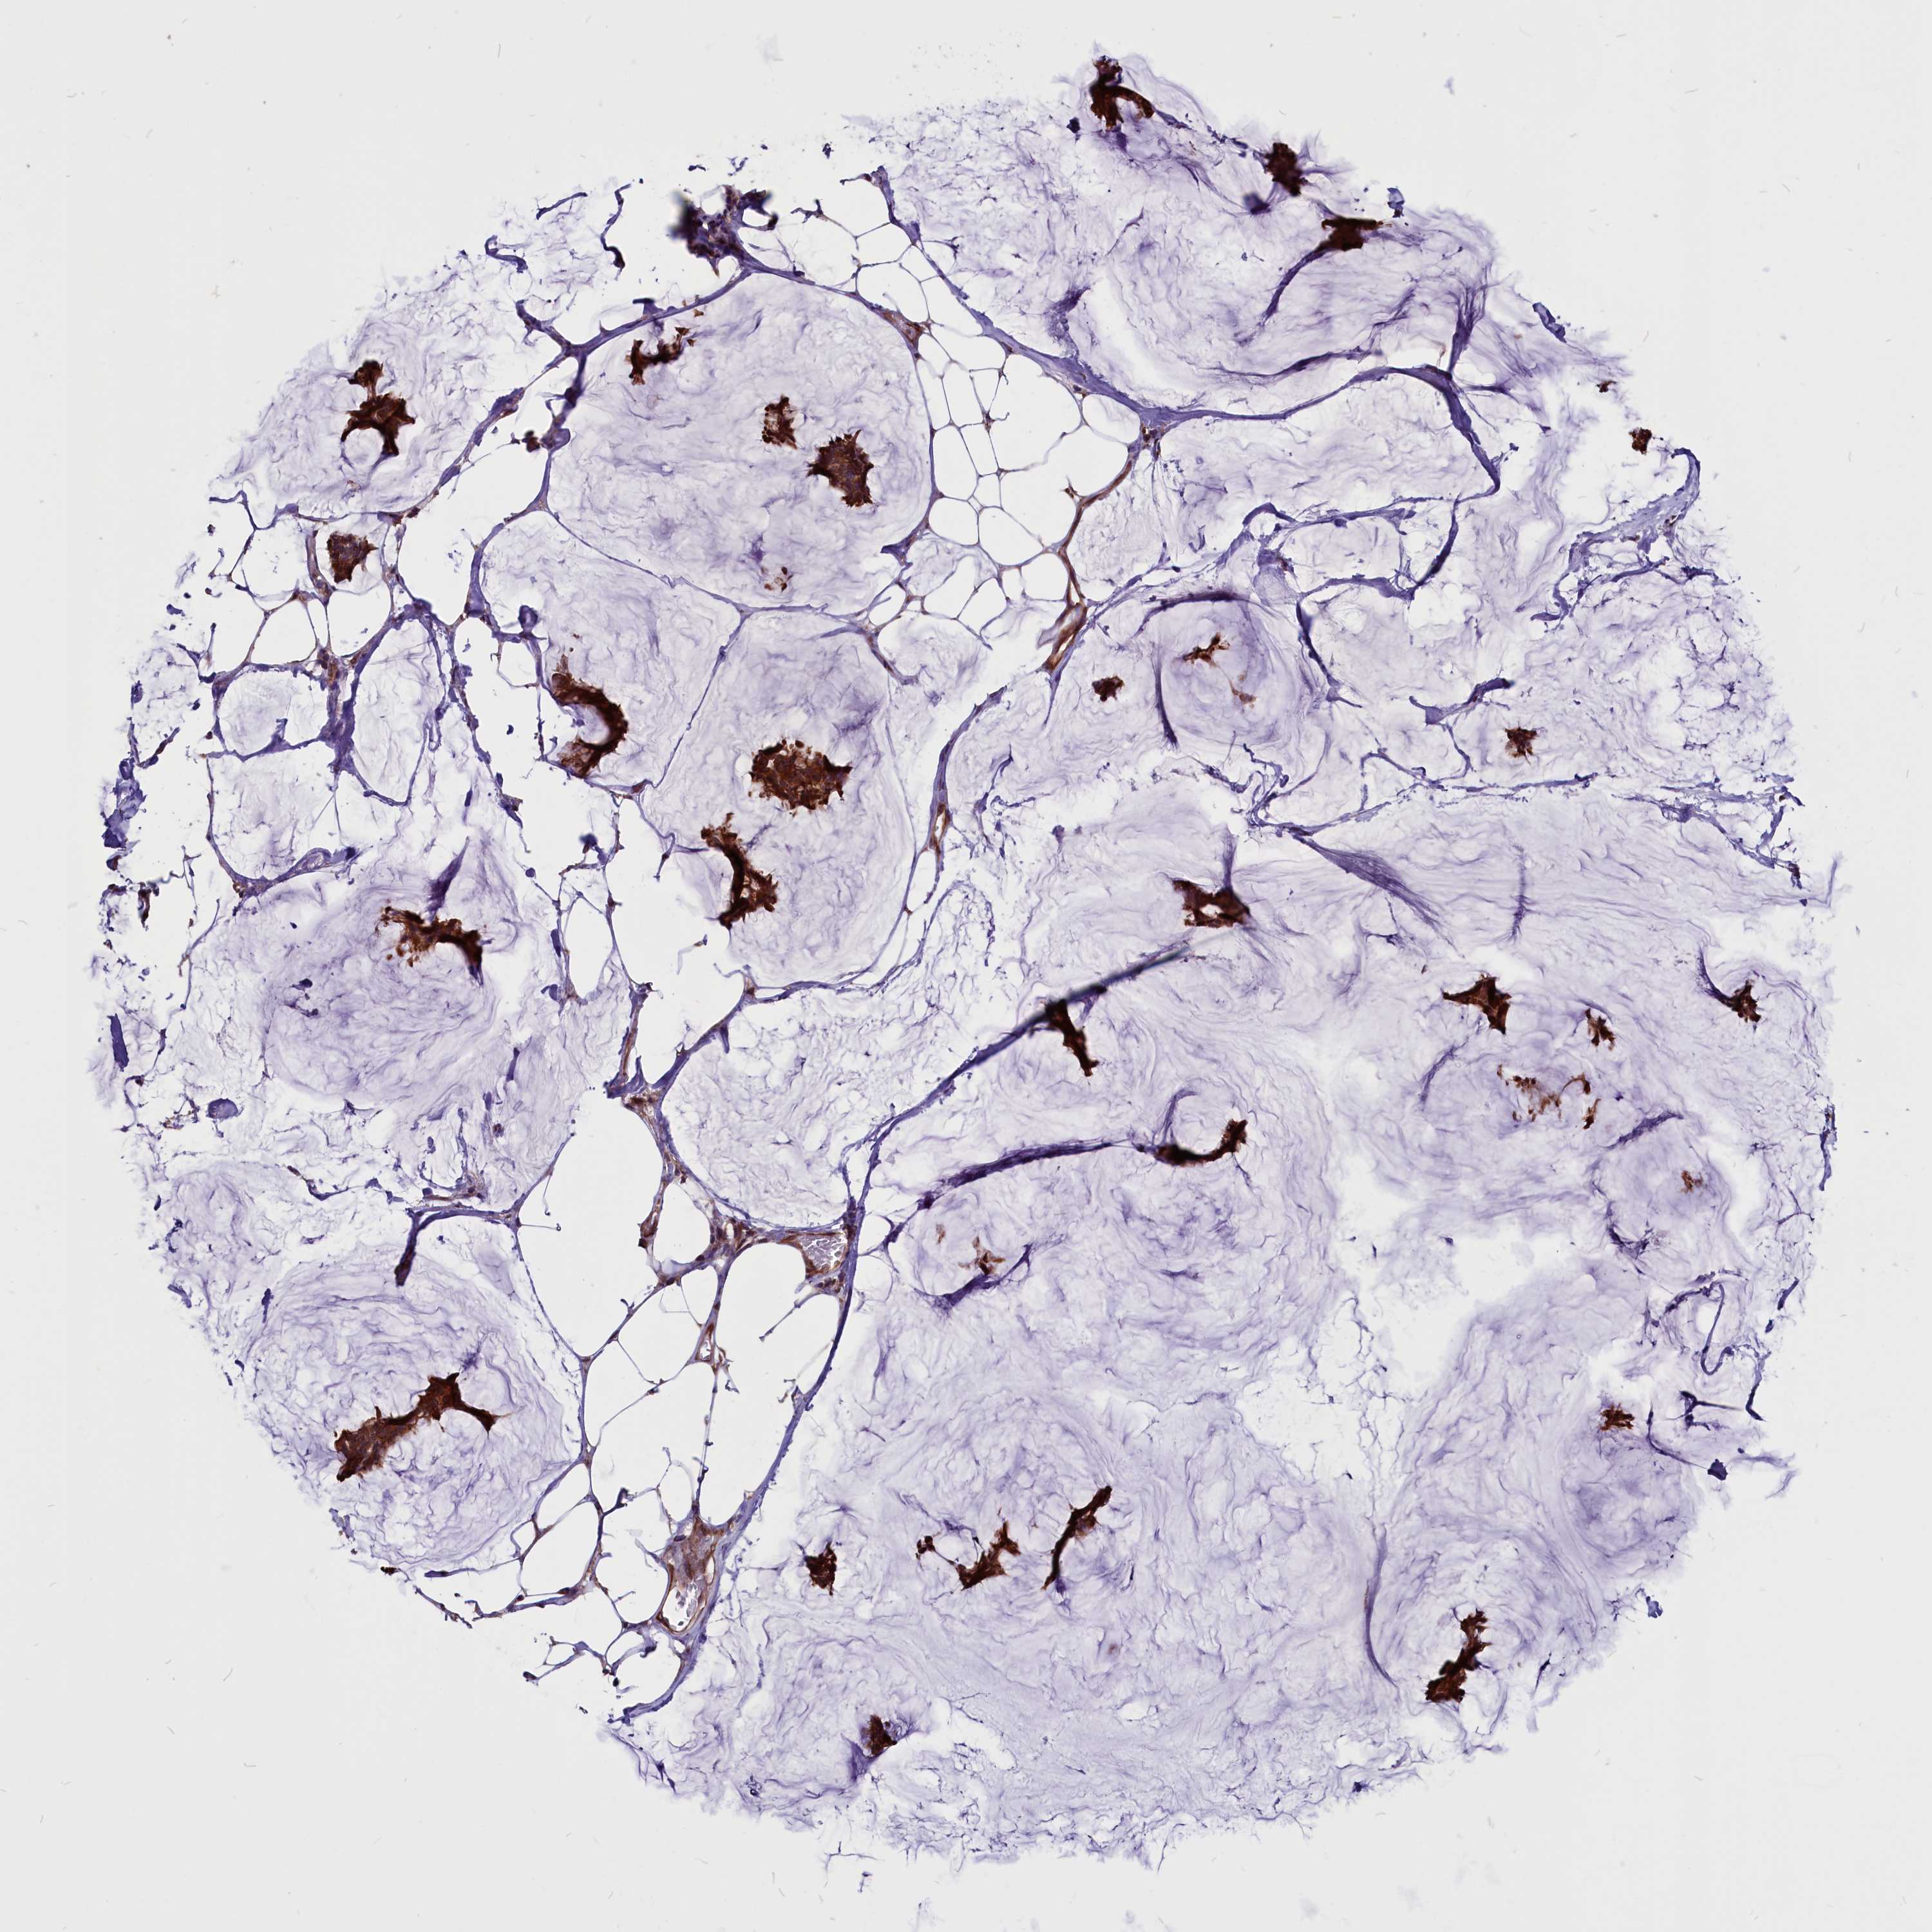

BRCA TCGA BRCA VALIDATION PROTEIN EXPRESSION

Breast cancer

Human cancer